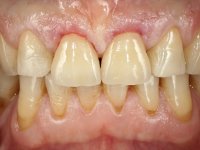

It was important to involve the patient in assessing the aesthetic advantage of increasing the height of central superior incisors. For this purpose, a direct mock-up was molded in-mouth, with non-adhesive composite resin. Once the patient agreed to the course of treatment, a silicon matrix was prepared, for subsequent production of provisional veneers. After installing a gingival deflection cord, dental preparation was performed, with special consideration to the fact that the insertion of both veneers would be frontal. Accordingly, mesial and distal walls did not require convergence. The incisal edge was prepared perpendicular to the axis of insertion. After preparation, IDS (immediate dentin sealing) was carried out. A “one-step, double mix technique” was adopted for impression, using putty soft and light silicon. Provisional veneers were produced using dual polymerization composite resin. Color selection was done in the same session.

The two feldspathic ceramic veneers, featuring frontal insertion axis, were produced in the lab, using a Geller type working model. Back in the clinic, after placing a rubber dam, the veneers were installed. A careful examination of the occlusion, with special focus on protrusion, was performed immediately after final bonding. The patient manifested a favorable aesthetic appreciation, regarding the retrieved dominance of the central incisors.